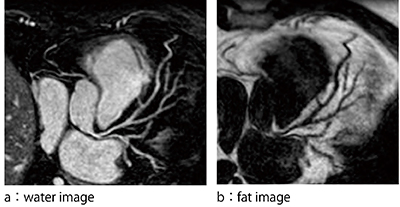

現在,mDIXON XDに期待されている領域は心臓領域,特に冠動脈撮像である。MRIによる冠動脈撮像は,balanced SSFPシーケンスにSPIR法などの脂肪抑制を併用したwhole heart coronary MRA(以下,CMRA)が広く臨床応用されている。mDIXON XDがCMRAにもたらす特長としては,高い脂肪水分離による画質向上が挙げられる。図1は,SPIR法を併用したCMRAとmDIXON XDを併用したCMRAのwater imageである。SPIR法を併用したCMRAは,心臓周囲脂肪のわずかな抑制不良が冠動脈の背景信号として存在しているが,mDIXON XDを併用したCMRAは精度の高い脂肪水分離により心臓周囲脂肪が抑制されていることが確認できる。SPIR法では単一脂肪の周波数のみに脂肪抑制パルスを照射するが,それ以外の周波数を示す複数の脂肪には対応していないため脂肪抑制不良を示している。一方,mDIXON XDは前述のとおり,脂肪のマルチピークモデルを採用していることからわずかな脂肪信号も排除し,冠動脈と周囲脂肪のコントラスト比が向上し,画質改善をもたらすことが可能である2),3)。また,mDIXON XDは,冠動脈を高信号に示すwater imageのほかに脂肪信号のみを反映したfat imageも再構成されるため,fat imageを用いた冠動脈外観の評価も可能である(図2)。例えば,water imageにより冠動脈狭窄が疑われた場合,fat imageによる血管外観を併せて観察することによりアーチファクトなどによる偽狭窄の判別が可能となり,さらなる診断能向上が期待されている。

図2 mDIXON XDによる冠動脈内腔と外観の評価